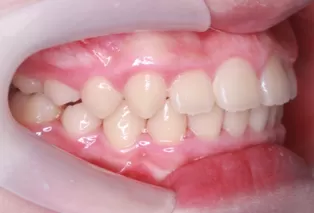

Photos intra-orales